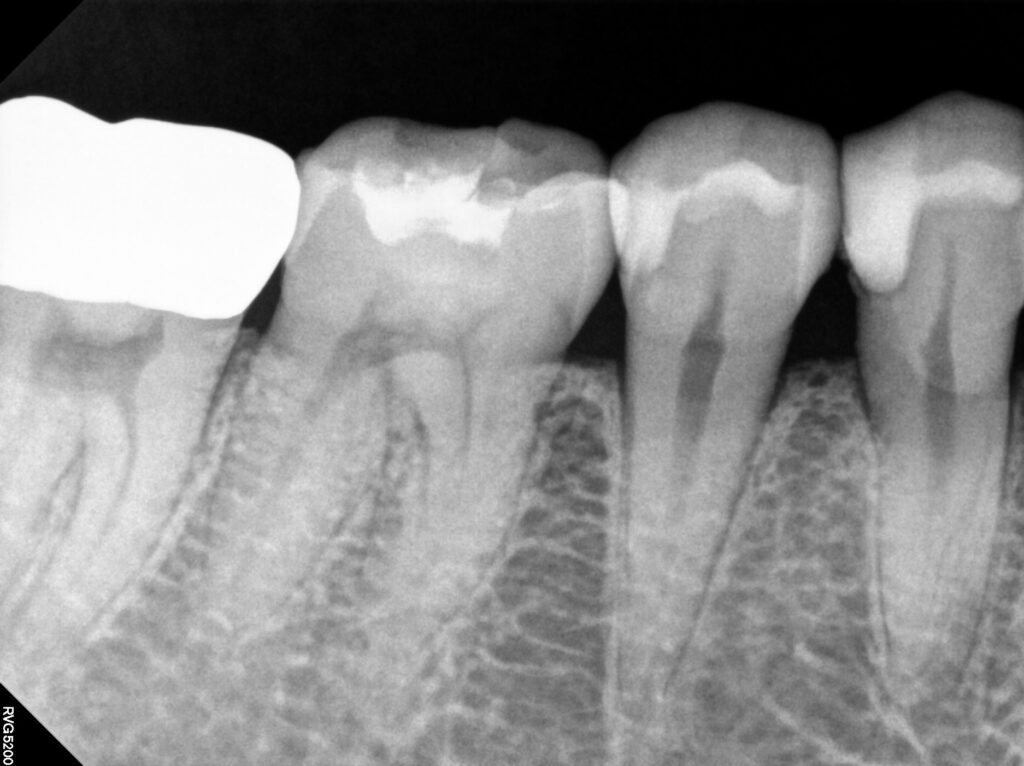

이번 증례에서는 구치부 치아의 손상으로 인해

레진 빌드업을 시행한 과정을 살펴보며,

치료 전 상태와 빌드업 과정,

그리고 회복된 결과를 중심으로

자세히 안내드리고자 합니다.